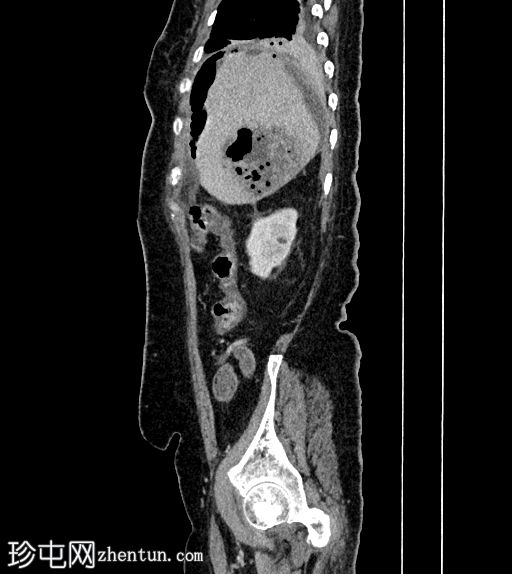

超声检查

2.png

肝胆系统

3.png

肝脏第6和第7段可见多个高回声气体腔,遮挡肝脏后部

肝脏其他部位形态及回声纹理正常

胆总管扩张,无结石,肝内胆管未见扩张

其他方面正常无游离液体